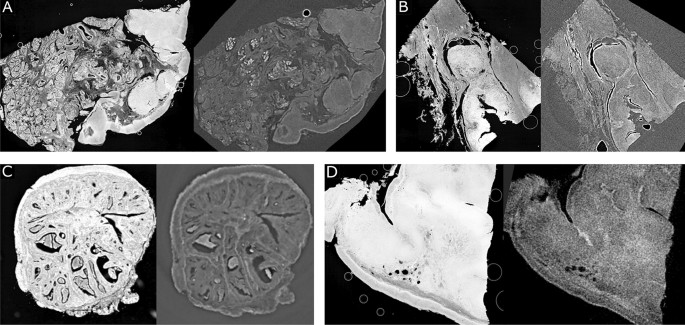

Preprocessed histology slides and the registered CT slices of different tissues and imaging modalities. (A) and (B) Tonsil tissues and phase-contrast CTs. (C) Tumor tissue and phase-contrast CT. (D) Tonsil tissue and absorption CT.

The registered images from 4 datasets are shown in Figure 2. The CTs in Figures 2A and B are the histology slides and phase-contrast µCTs of tonsil tissues acquired at Exciscope. The initial spacing of the CT volumes is 2.6 µm. Figure 2C shows the histology slide and the phase-contrast CT of tumor tissue acquired with the TOMCAT beamline at the synchrotron setup at Paul Scherrer Institut29, with a spacing of 1.6 µm. An absorption µCT acquired at MITOS GmbH30 and the corresponding histology slide are shown in Figure 2D. It shows visually good registration on various tissue types (tonsil, Figure 2A, B, D, and tumor tissues, Figure 2C) and imaging modalities (absorption, Figure 2D, and phase-contrast CT, Figure 2A, B, C), which indicates the proposed method has the potential to be further applied to different tissues and imaging modalities without retraining the model. All the registration results demonstrate visually good registration of the proposed approach, especially on the macro structures.